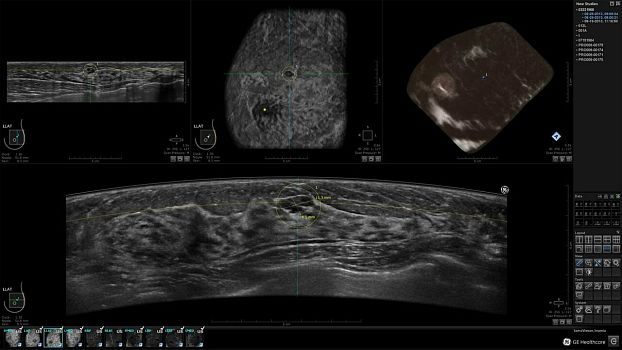

Клинические изображения

• Отображение объемных 3D ультразвуковых изображений, которые состоят из традиционных поперечных и воссозданных коронарных и сагиттальных проекций

• Многооконный просмотр: 4 - 12 изображений.

• "толстый срез" в коронарной плоскости;

• поперечная;

• сагиттальная плоскость;